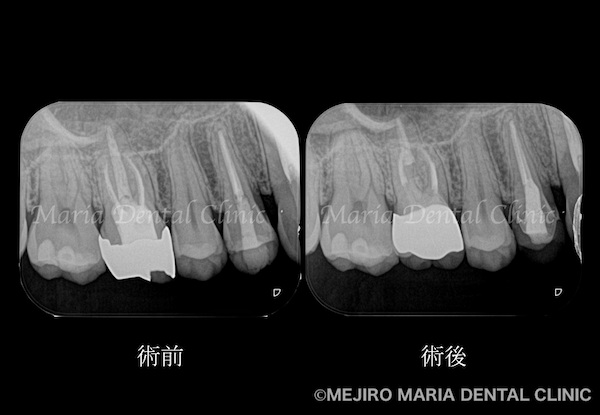

を併発した根尖性歯周炎を、精密根管治療で治癒|術前の歯のレントゲン画像_治療前1.png)

治療のコンセプトに沿って精密根管治療を2回で終了させ、暫間冠(仮歯)にて3ヶ月間の経過観察を行いました。3ヶ月後には症状は完全に消失、セラミック冠を装着して今後2年間の経過観察を行うこととしました。

を併発した根尖性歯周炎を、精密根管治療で治癒|治療前後の歯のレントゲン比較画像_治療後1.png)

精密根管治療から1年後の経過観察にて、患者様が初診時に訴えていた症状が消失していることを確認しました。

その結果、術前に見られた上顎洞に広がる不透過像(グレーの部分※膿)はほぼ消失していることが確認でき、予後は良好であると判断しました。